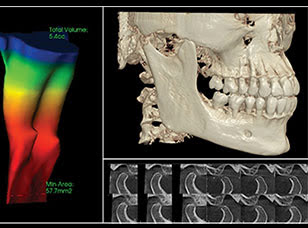

「CT」を活用することで、三次元での撮影が可能になります。

通常のレントゲンは二次元のため、詳細な骨の厚さや血管・神経の位置などまでは確認することができません。

しかし、CTはこれらを撮影できます。

歯科治療において、「見える/見えない」は治療結果に大きく影響するため、CTを活用することで、治療精度向上に努めています。